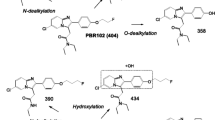

Synthesis of [18F]SF51 from a diaryliodonium salt [11] has previously been described. For this study, [18F]SF51 was prepared by a new method based on radiofluorination of a diarylselenone precursor according to a protocol recorded in FDA-sanctioned eIND #162,310. Detailed information regarding synthesis of the precursor and radiosynthesis will be published separately.

Radiochemically stable [18F]SF51 was obtained for intravenous injection in sterile saline containing ethanol (10% v/v) in a total volume of 10 mL (Fig. 1). All preparations of [18F]SF51 had high radiochemical purity (> 99% by radio HPLC) and molar activity between 88.5 and 126 GBq/mmol (2.39 – 3.42 Ci/mmol).